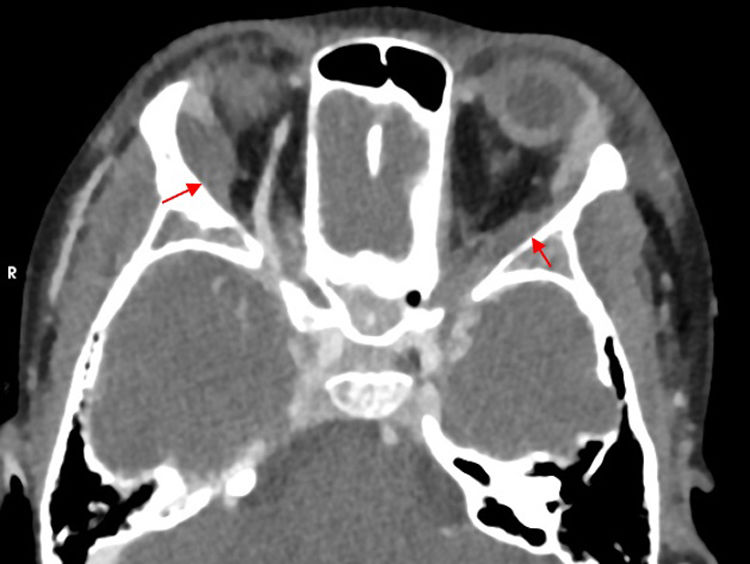

Paciente de 8 años con enfermedad de células falciformes homocigota (sin antecedentes familiares), tratada con amoxicilina profiláctica, hidroxiurea y ácido fólico, en seguimiento anual y con un ingreso previo por crisis vasooclusiva en pierna, sin otros antecedentes. Ingresa con sospecha de crisis vasooclusiva en extremidades y abdominalgia en hospital de origen, y se deriva a nuestro centro por deterioro progresivo, con fiebre, hepatomegalia y esplenomegalia hasta cresta ilíaca, así como tumefacción dolorosa periocular bilateral, sin flogosis ni alteración visual (fig. 1). Analítica con descenso de hemoglobina y plaquetas, elevación de parámetros de hemólisis, HbS 44,3% y PCR de 17,7mg/dL. Sospecha de secuestro esplénico y celulitis orbitaria1,2, se administran oxigenoterapia, analgesia en perfusión contínua de morfina, dos transfusiones de hematíes y antibioterapia endovenosa. TAC de órbita (fig. 2) con componente de partes blandas en región periorbitaria externa bilateral, siguiendo el margen óseo y con extensión posterior, compatible con posible hematopoyesis extramedular o proceso linfoproliferativo. RMN craneal (fig. 3) descarta afectación nerviosa mostrando áreas sugestivas de infarto en alas mayores esfenoidales y efusiones hemorrágicas secundarias3. Hemocultivo y serología a VEB negativos. Se orienta como infarto óseo y se suspende antibioterapia, con mejoría clínica completa a los siete días.